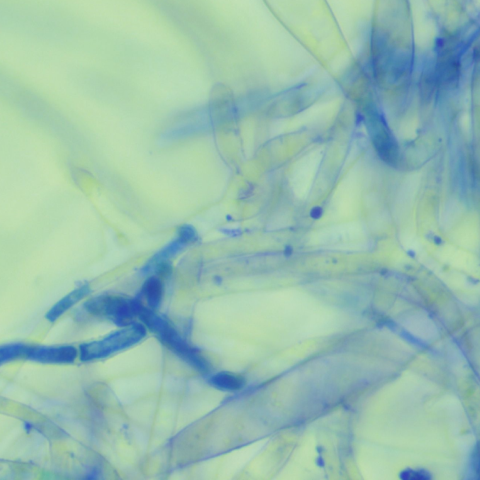

ÇǺΠµµ¸»°Ë»ç, °õÆÎÀÌ ¹èÁö °Ë»ç µîÀ» ÅëÇØ °¨¿°ÀÇ ¿øÀÎÀ» ã¾Æ¾ß ÇÕ´Ï´Ù. ¾Ë·¯Áö°¡ ÀǽɵǸé Ç÷¾×°Ë»ç¸¦ ÅëÇØ ¾Ë·¯Áö °Ë»ç¸¦ ÁøÇàÇÕ´Ï´Ù.